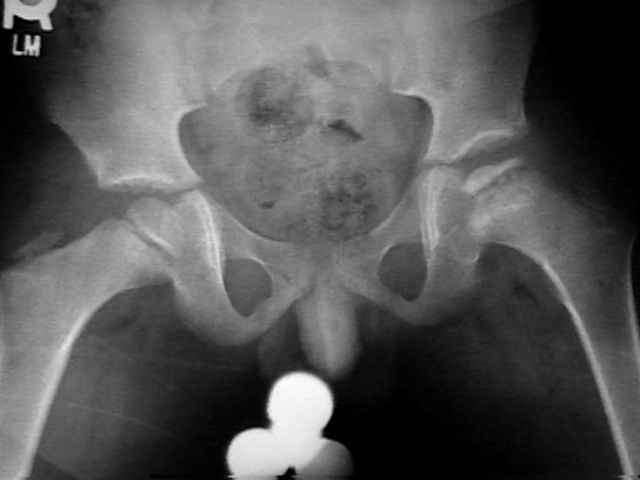

В основе диагностики болезни Легга-Пертеса лежит рентгенологическое исследование сустава, с его помощью специалисты определяют стадию и степень деформации. Согласно полученным результатам врач выбирает оптимальные способы лечения. Дополнительными диагностическими методами служат:

Рентгенологическое обследование

При подозрении на болезнь Пертеса делают не только снимки в стандартных проекциях, но и рентгенограмму в проекции Лауэнштейна. На основании полученных результатов исследования врач ставит диагноз, чаще всего используя классификации Сальтера-Томсона и Кэттерола.

Ортопед, изучая рентгенограмму, выявляет особенности строения костей и степень деформации суставной головки.

Снимки позволяют увидеть метафизарные изменения, линию субхондрального перелома и другие патологии.

Полученные рентгеновские снимки позволяют изучить особенности строения костной ткани, но на начальной стадии болезни не позволяют оценить степень поражения мягких тканей и костных структур. Диагностировать болезнь Легга-Кальве -Пертеса у маленьких пациентов можно с помощью МРТ или компьютерной томографии тазобедренного сустава.

КТ определяет начальные изменения в головке бедренной кости. На экране компьютера врач видит послойные снимки проблемного участка, что позволяет выявить характерные для асептического некроза состояния, к примеру отек костного мозга.